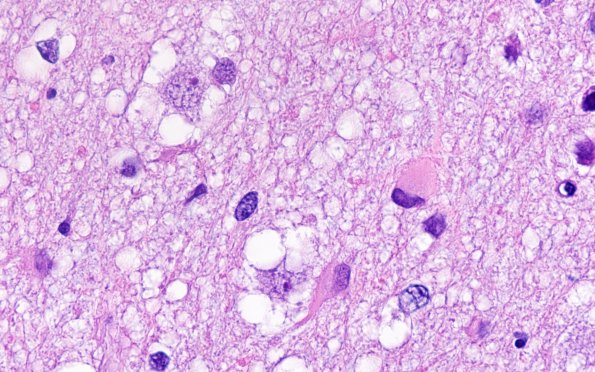

Washington University Experience | NEOPLASMS (NEURONAL) | Multinodular Vacuolating Neuronal Tumor | 3B9 MVNT (Case 3) H&E 100X 1

3B9-12 Astrocytes have a gemistocytic or fibrillary appearance in these high magnification images. The vacuolation of these neurons remind me of the olivary hyperplasia alteration sometimes designated “mulberry-like”. (H&E)